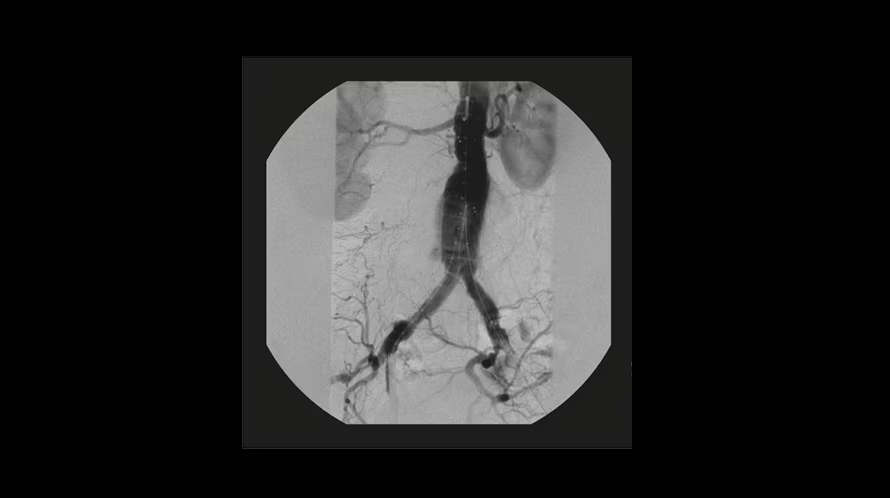

GE OEC Elite CFD относится к мобильным рентгенохирургическим системам премиум-уровня и предназначена для проведения интраоперационных рентгеноскопических и рентгенографических исследований в хирургии, травматологии, ортопедии, сосудистых и эндоваскулярных вмешательствах, нейрохирургии и урологии. Плоскопанельный КМОП-детектор с полем обзора 21×21 см, высоким динамическим диапазоном и частотой до 30 кадров/с обеспечивает детализированную визуализацию костных структур, мягких тканей и контрастированных сосудов в режиме реального времени. Передача изображения 1:1 на 32-дюймовый 4K-монитор просмотровой станции позволяет хирургу уверенно ориентироваться в операционном поле, контролировать положение инструментов и имплантов, минимизируя количество повторных экспозиций.

- Интеллектуальные профили обработки: общая хирургия, ортопедия, спинальная хирургия, контрастные исследования, ангиография, кардиография.

| Цифровая субтракционная ангиография (DSA) | Вычитание фоновых структур для повышения видимости сосудистого русла при контрастных исследованиях. |

| Сосудистые и навигационные режимы | Специализированные профили (Vascular, Cardiac, Roadmapping) для визуализации сосудов и навигации проводников. |